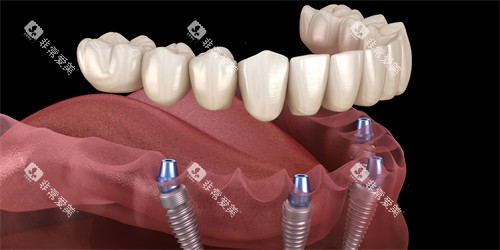

种植牙